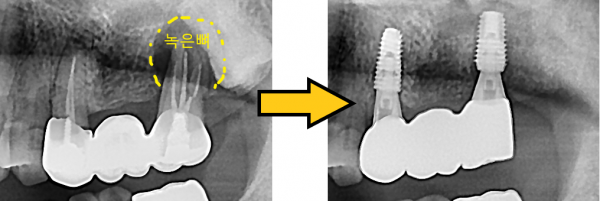

임플란트 뼈이식 + 임플란트